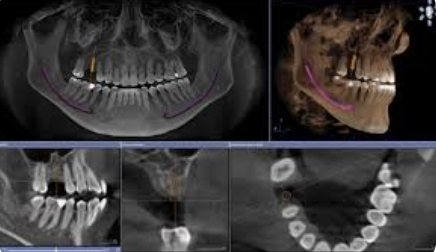

• Компьютерная томография (КТ) — это как 3D-модель вашего зуба или челюсти, которую можно покрутить на экране компьютера, рассмотреть со всех сторон, разрезать на тончайшие слои и заглянуть внутрь.

Во время процедуры специальный аппарат (он называется конусно-лучевой компьютерный томограф, или КЛКТ) делает сотни снимков под разными углами всего за 10-20 секунд. Затем компьютер собирает их в единую, невероятно детализированную трехмерную картину. Для вас это выглядит просто: вы несколько секунд сидите или стоите неподвижно, пока сканер вращается вокруг головы. Никакого дискомфорта.

• С КТ: Врач видит челюсть в 3D. Он может виртуально «примерить» имплантат на компьютере, выбрать идеальный размер и угол, обойти все опасные зоны. Это превращает операцию из искусства в точную науку.

• С КТ: Врач видит точное 3D-положение корней относительно нерва и может спланировать удаление так, чтобы избежать любых повреждений.